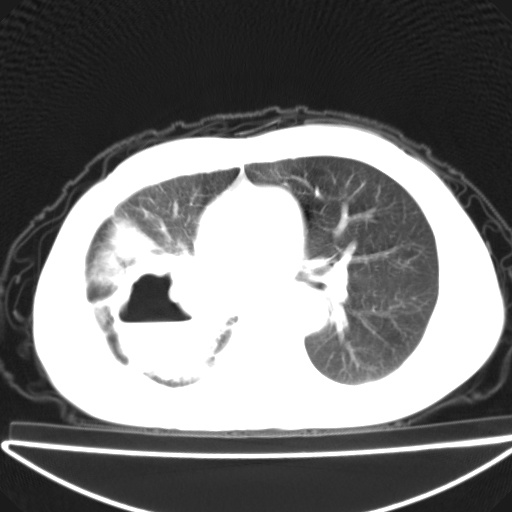

以下是引用jsgdoctor在2008-11-6 22:12:00的发言:[br]右主支气管壁明显增厚,管腔狭窄.考虑为右侧中央型肺癌伴阻塞性炎症\\肺脓肿.

以下是引用zjzjr在2008-11-6 20:25:00的发言:[br]中心型肺ca,合并阻塞性肺炎

以下是引用zsl6918在2008-11-6 19:43:00的发言:[br]右侧中心性肺癌(鳞癌)